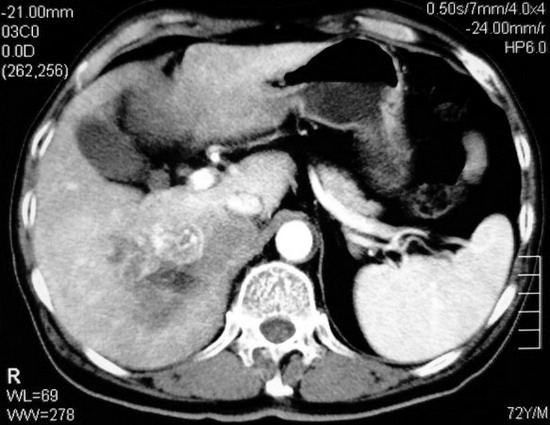

以下是引用杀毒软件在2008-11-17 19:15:00的发言:[br]考虑------右肾癌合并肾静脉---同侧肾上腺受侵可能性大

以下是引用zjzjr在2008-11-17 20:45:00的发言:[br]考虑------右肾癌合并肾静脉---同侧肾上腺受侵可能性大及腹膜后淋巴结转移.